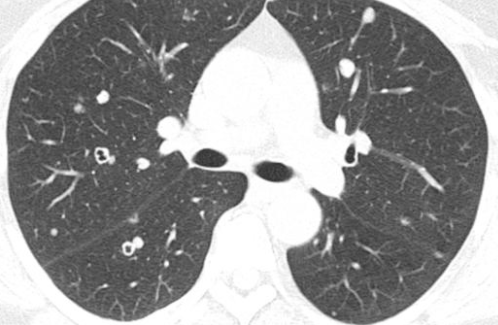

En Miliaire

- Tumeur vascularisées: rein, sein, mélanome, thyroïde